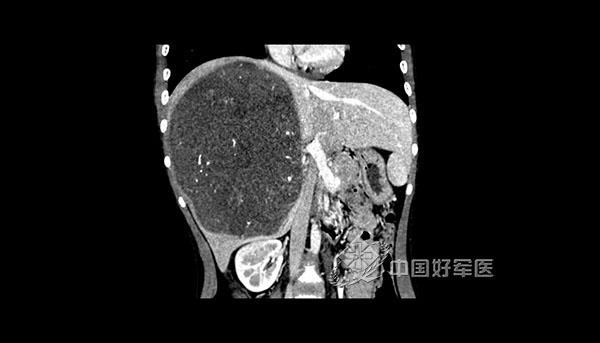

12岁的馨馨家住四川合江,半月前始出现全身乏力、肚子胀、低烧等症状并迅速加重,家人带其前往当地某三甲医院,检查发现肝上有一巨大肿瘤,由于肿瘤占据了大部分肝脏,手术风险极高,馨馨一家抱着一线希望辗转来到新桥医院。经过进一步检查诊断馨馨患的是非常罕见的胚胎性肉瘤,直径达15cm,巨大的肿瘤压迫了胃肠道。切除肝脏太多容易导致剩余肝脏代偿不够,进而发生术后肝衰竭,到底有没有希望手术呢?12岁的小生命就在眼前,用科学敬畏生命乃医者的信仰之本。为了进一步确定治疗方案,肝胆外科召集儿科、肿瘤科、消化科、放射科、麻醉科、整形美容科等院内专家进行了全院会诊,经过反复讨论,专家们判断馨馨所患肿瘤恶性程度非常高,手术切除是其获得长期存活的唯一机会,如果采用先进的术前影像三维重建技术将其现有的CT影像在电脑上生成直观的三维模型,模拟手术并为其精确设计出仅保留20%肝体积的极量肝切除作为手术方案,使手术成为可能。

据新桥医院肝胆外科副主任郑璐介绍,肝脏是人体重要器官之一,任何肝脏病变切除手术的前提是需要保留足够体积的肝脏维持患者术后的正常生理代谢,“极量”肝切除是指肝脏切除的范围达到全肝体积75%左右的肝手术,实施极量肝切除术后发生急性肝衰竭的风险非常高。具体到馨馨这个病例,一是要彻底,需要切除占据肝脏80%体积的病灶,达到肿瘤的外科学根治;二是要精准,手术切除线避开肝内大血管,严控手术出血,还需要完整保留剩余20%健康肝脏的出入肝的血管和胆管系统,确保残余肝能够维持正常的人体生理功能。外科医生需要在手术疗效和风险之间找到精确的平衡点,这就对肝切除手术方案精准设计和医生的手术操作提出了极高要求,术前影像三维重建技术将其现有的CT影像在电脑上生成直观的三维模型并可模拟手术,尽可能的降低手术风险,存留的健康肝脏具有一定的再生功能,度过术后1周左右的危险期后,医生们才能暂时松一口气。